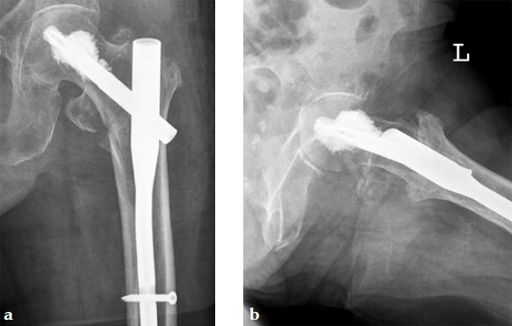

An 82-year-old woman with an unstable pertrochanteric fracture of the right proximal femur. Her Barthel Index was 80 and her preoperative Parker mobility score was 5, which means that she was walking at home unassisted. The patient's preoperative Parker mobility score of 5 was reached again at the 3-month follow-up.